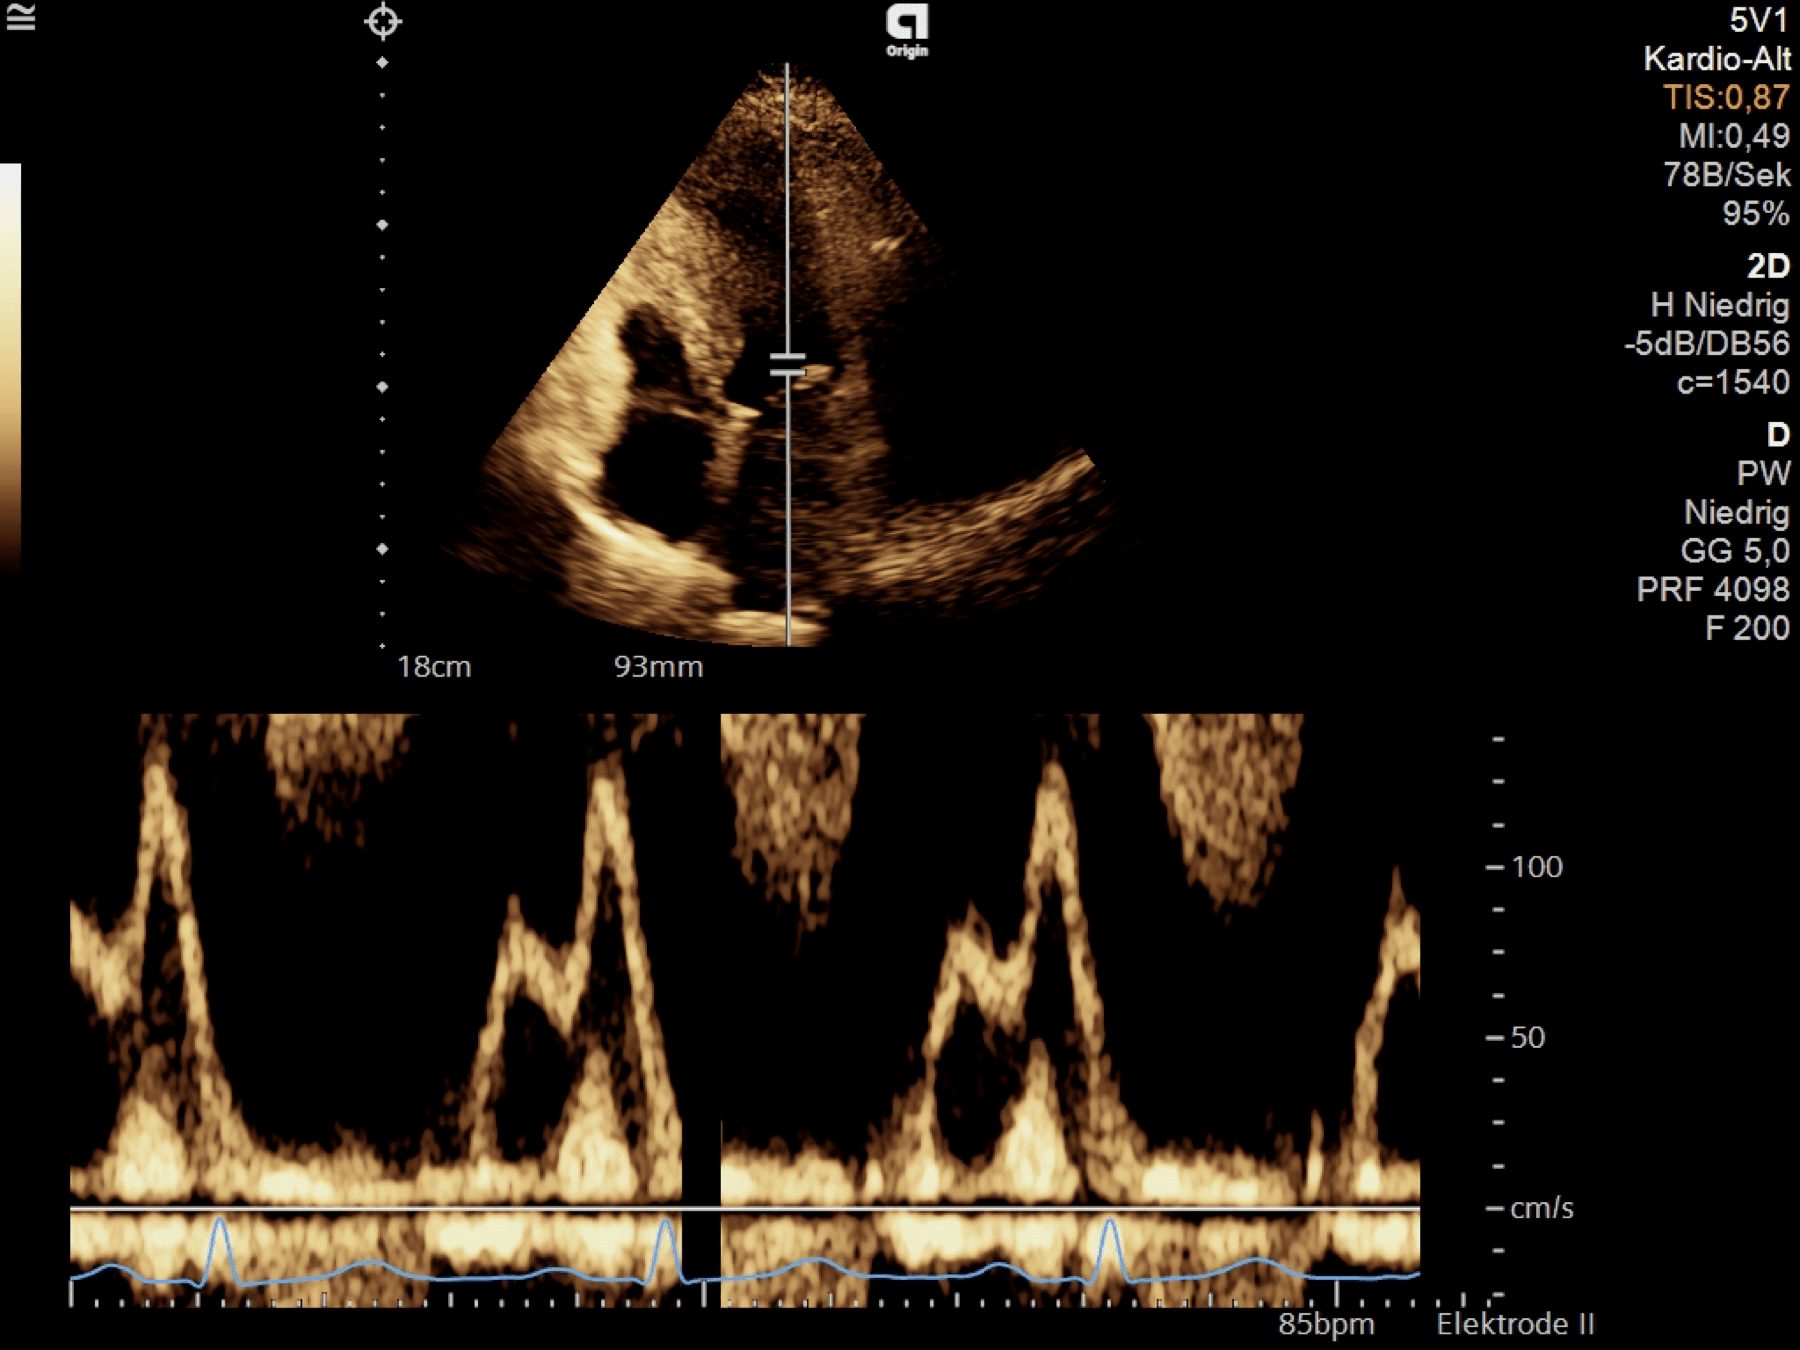

Atrial contraction (A-wave)

LA contraction elevates LV pressures ➜ MV opens again, LV fills with blood again

In normal filling pressures, almost no „counterpressure“ from the LV, a little bit of blood flows back to the PV, 10-20% of the blood is transported with <5mmHg of pressure

The LVEDP, LAP, PV, and pulmonary pressures are low